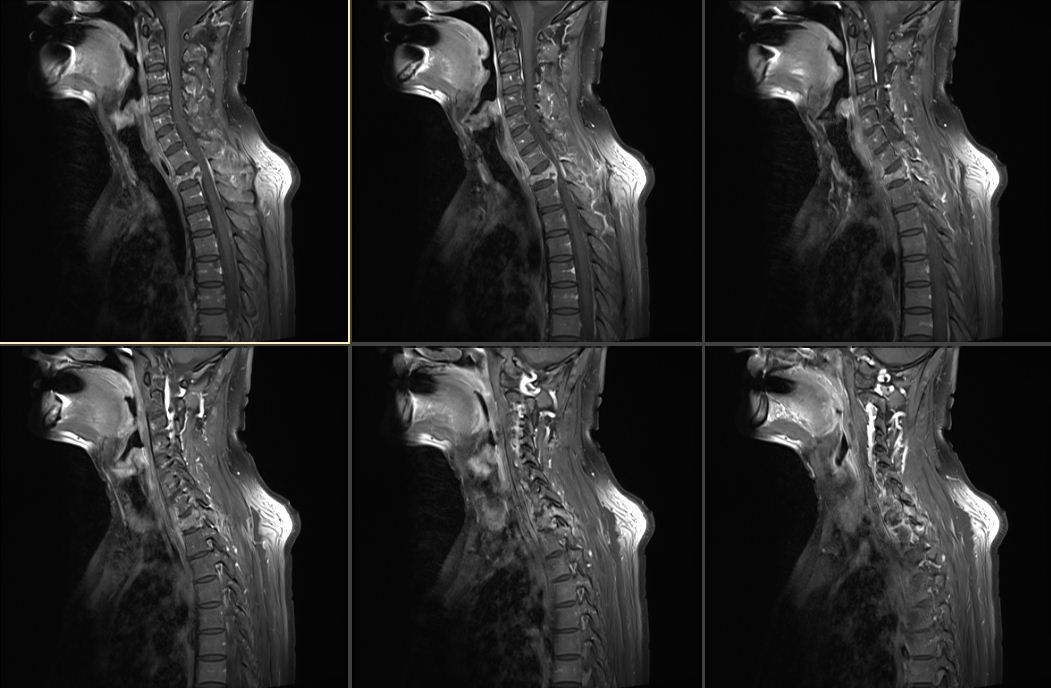

入院后,胸椎增强磁共振示胸6-8椎体层面椎管后缘梭形异常信号-考虑髓